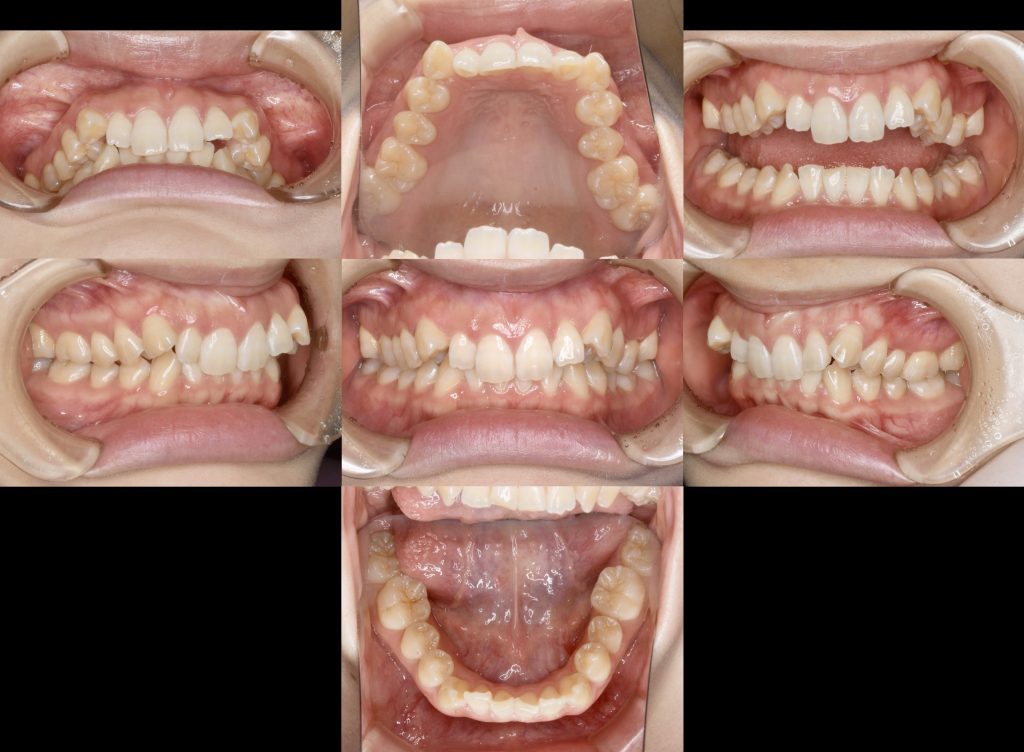

下記の症例は治療途中にはなりますが、マウスピース型では難易度が高いと言われる抜歯矯正となります。

当医院では術前検査・診査に時間を割く事で1本ずつの歯をどの程度動かせば良いか理解する事で、確実な治療結果をお約束する事ができます。